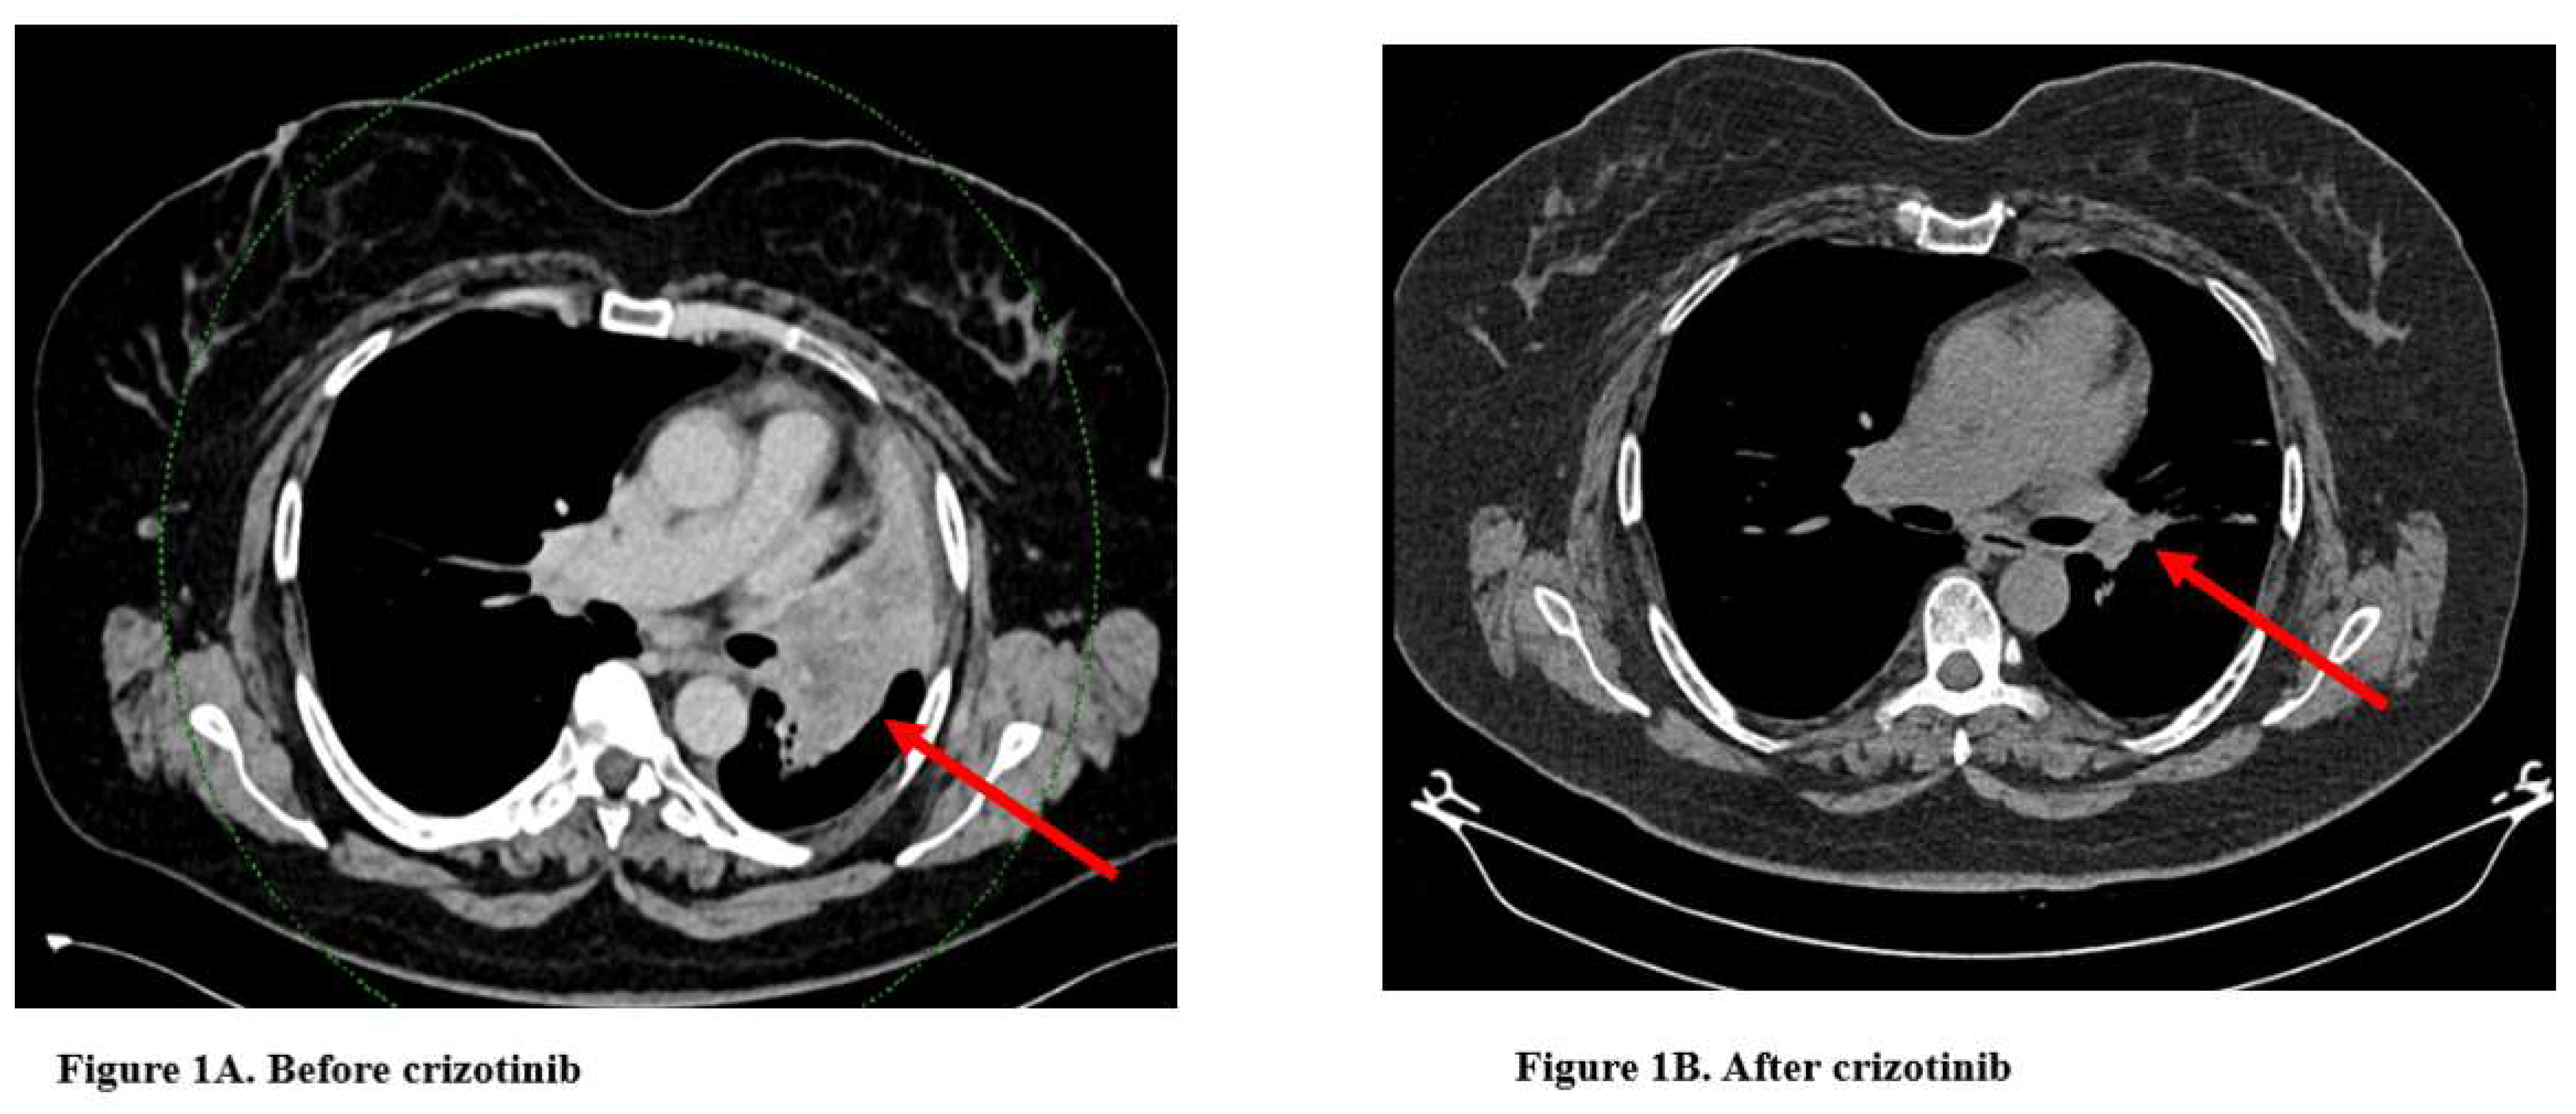

In October 2024, the patient was initiated on crizotinib 2×250 mg tablets, based on the results of the NGS. Within two weeks of treatment, the patient exhibited significant symptomatic relief and substantial tumor regression. No drug-related adverse events were observed. At the three-month follow-up, thoracic CT imaging demonstrated a marked reduction in tumor size compared to three months earlier, accompanied by a completely asymptomatic clinical response. The patient's thoracic CT images before and after treatment are presented in Figure 1, and the PET-CT image at the time of diagnosis is shown in Figure 2.

Figure 1. Thoracic CT, (A) Before crizotinib: A right hilar mass (red arrow), likely representing a tumor or lymph node enlargement, causing partial compression of adjacent structures. (B) After crizotinib: Significant reduction in the size of the right hilar mass (red arrow), indicating a positive therapeutic response.